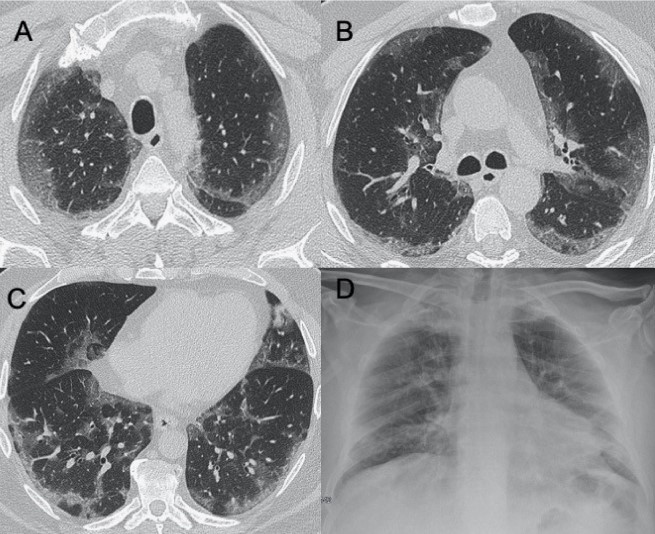

● CXR:肺胸膜下實變、磨玻璃影、結節和網狀結節陰影,表現為間質性肺炎伴彌漫性肺泡損傷(圖1)。

圖1 新冠肺炎(COVID-19)的CXR。3例仰臥位CXR顯示胸膜下實變(箭頭),圖(A,B)顯示雙側受累,(C)主要為右肺受累